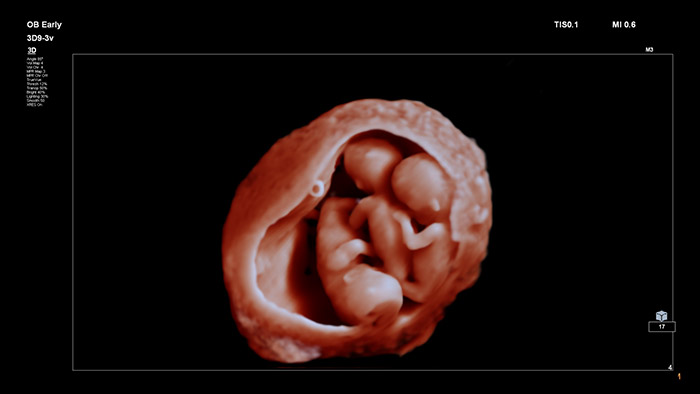

Imágenes realistas:

Gracias a sus imágenes innovadoras y con un alto nivel de detalle, así como a la posibilidad de manipular un fotoemisor virtual, TrueVue ofrece imágenes increíblemente realistas del feto durante el embarazo tanto a los profesionales sanitarios como a las futuras madres.